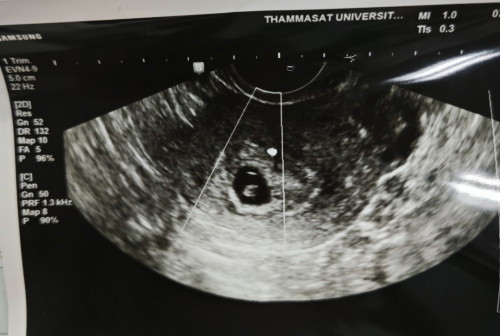

8 วีค+ยังไม่เจอหัวใจ

8 วีค+ยังไม่เจอหัวใจเลย มีใครเจอหัวใจมากกว่า 8 วีคมั้ยคะ ใจไม่ดีเลยค่ะท้องแรก ติดจากการทำเด็กหลอดแก้ว ปล.น้อยขนาดเท่า 6 วีคค่ะ

ถ้าติดจากการทำเด็กหลอดแก้ว จะไม่มีปัญหาเรื่องนับอายุครรภ์พลาดแบบท้องปกติ ที่ไข่อาจจะตกช้านะคะ คุณแม่อาจจะต้องเผื่อใจไว้ 50/50 นะคะ เป็นกำลังใจให้นะคะ ก่อนใส่ตัวอ่อน ได้ตรวจโครโมโซมตัวอ่อนมั้ยคะ

แม่ซาวทางช่องคลอดไหมคะ ถ้าใช่คงหมดหวังแล้วค่ะ (ของบ้านนี้หมอแจ้งว่าซาวทางช่องคลอดผลจะชัดเจนที่สุด เคยผ่านมาเหมือนกัน น้องแฝดด้วย)

ทางช่องคลอดค่ะแม่